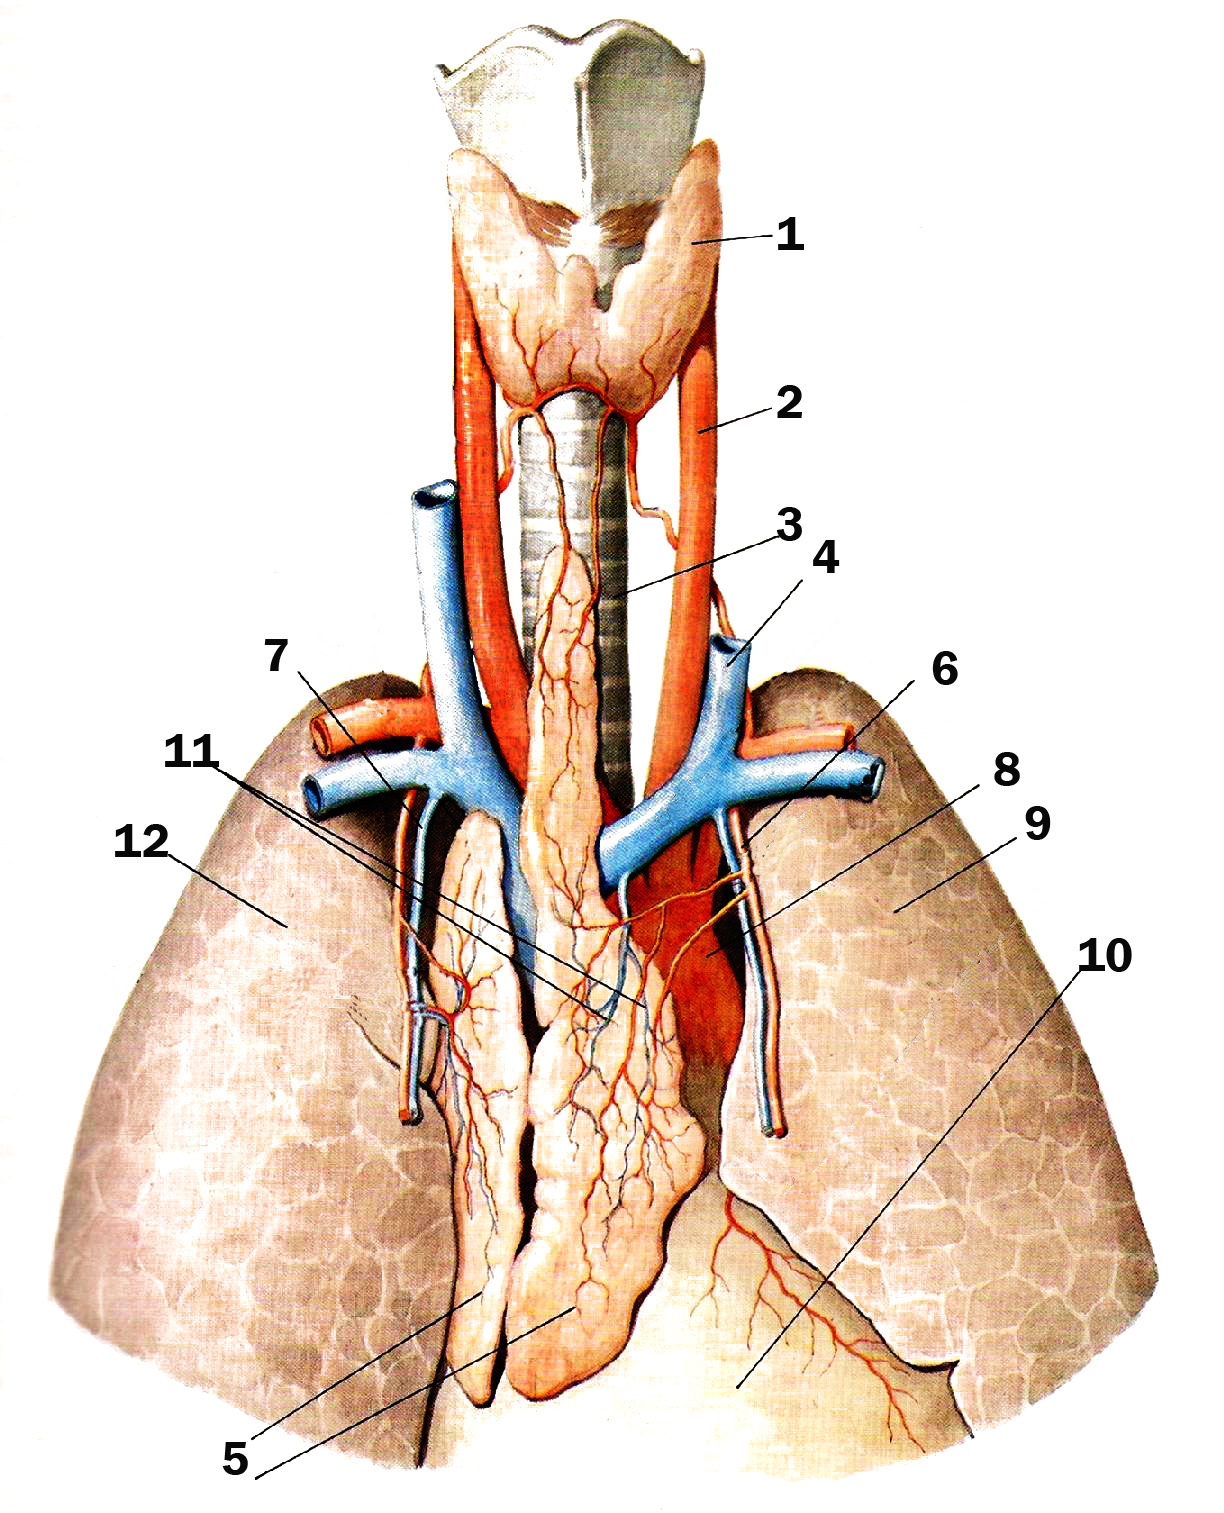

Фотографии вилочковой железы тимуса: структура и функции